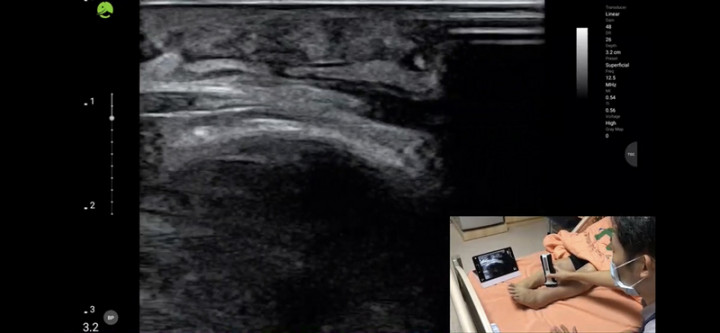

台大醫院與台北市立聯合醫院中興院區4日舉辦「跨院遠距通訊診療」線上記者會,雙方將強化合作,中興院區醫師可透過即時超音波與台大醫院醫師共同會診。(台大醫院提供)

此外在科技協助下,遠距醫療更便利,如即時超音波技術被稱為「新世紀的聽診器」,許甯傑說,傳統聽診器或超音波很難分享資訊,但隨著科技進步,不僅可即時分享影像,還能讓多名醫師參與討論病情,讓病人得到更全面的照顧。